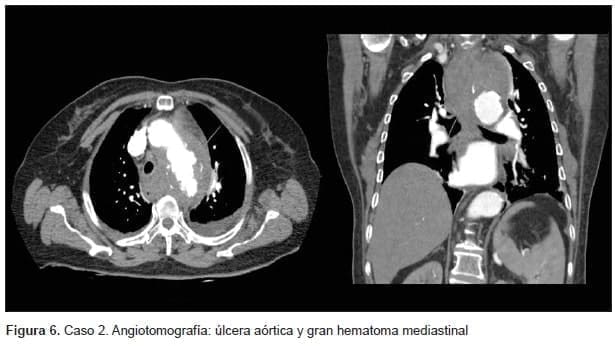

Durante la hospitalización, la paciente presentó descompensación hemodinámica con aumento del dolor torácico. Se descartó un proceso coronario agudo y se tomó una angiotomografía de tórax por sospecha de tromboembolia pulmonar. Demostró un aneurisma sacular originado en el cayado aórtico, con signos de ruptura como un hematoma contenido en mediastino superior y ausencia de llenado de la arteria subclavia izquierda (figura 6).